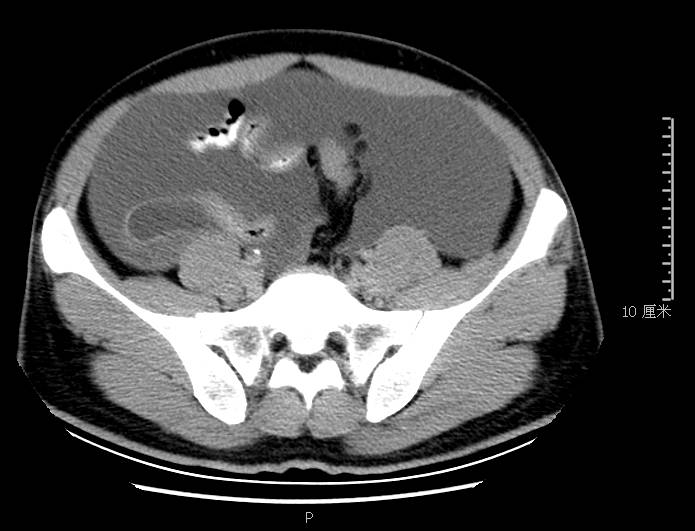

全腹CT:(1)结合病史考虑腹膜炎(见图2A),大量腹水;(2)右骼窝区管状样结构,考虑阑尾扩张(见图2B);(3)肝脏多发小囊肿(见图2C);(4)肝内胆管轻度扩张,建议隔期复查。

图2b扩张成管状阑尾

本例确诊后对B超及CT再次回顾发现:腹腔、盆腔可见不均质中强回声包块,部分呈囊实状,腹膜增厚,大网膜成饼状(如图2A)和肝周可见不均质中强回声弧形压迹、脾周可见不均质中强回声包饶,肝脏成扇贝样改变(如图2C),但在诊断报告中未提及。有学者发现mantle和scalloping(如图2A,2C)在PMP中具有代表性,且mantle较scalloping更为常见,若mantel征同时伴有大小不一的囊性改变,则更具诊断价值。

与此同时,还应与肝硬化腹水、妇科肿瘤、肠梗阻等疾病相鉴别。此患者为男性,全腹CT及PET-CT均提示阑尾扩张,很大可能来源于阑尾黏液性肿瘤。阑尾黏性肿瘤早期可无任何症状,随着瘤体堵塞阑尾,累及浆膜下层,播散至腹盆腔,可形成大量的黏液性腹水,又称“胶腹”,则可出现腹痛、腹胀、腹围增加等症状。

通过本病例分析认为此类患者,腹穿时若发现腹水不易抽出或抽出物为黏稠胶冻样,腹部B超提示液性暗区内有漂浮的团状回声有分隔,撞击腹部后可出现“礼花”样改变,肝脾包膜完整不光滑,有弧形压迹,全腹部CT示弥散占位,可见mantle和scallping征、大网膜成饼状且阑尾扩张应高度怀疑本病。